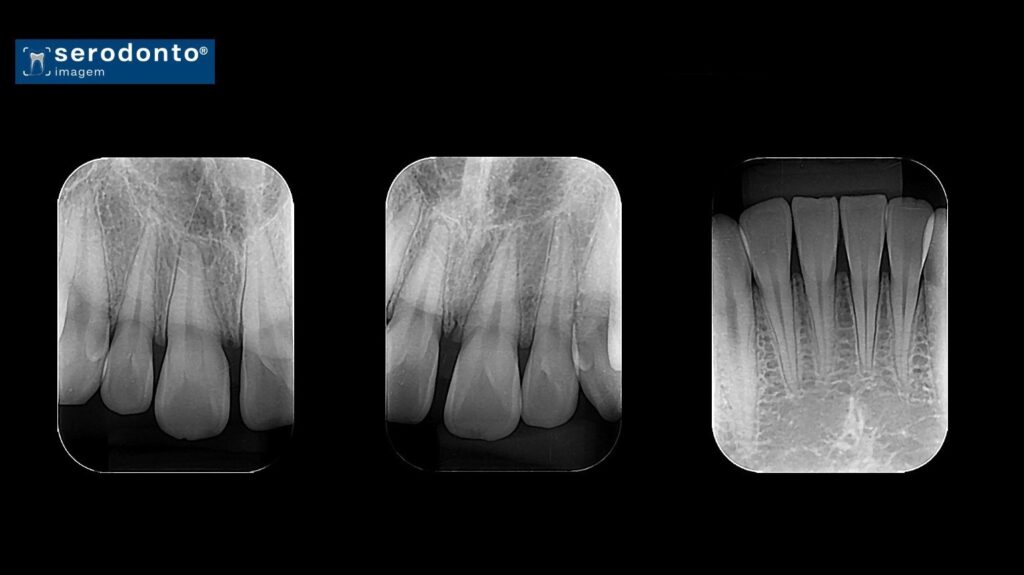

Radiografia Periapical

A radiografia periapical oferece uma visão detalhada da coroa, raiz e estruturas adjacentes de um ou mais dentes.

• Identificação de lesões periapicais.

• Avaliação de cáries e fraturas dentárias.

• Planejamento de tratamentos endodônticos.

• Monitoramento de condições periodontais.